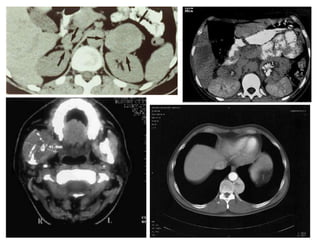

TAC c/contraste

++++

+++

RMN